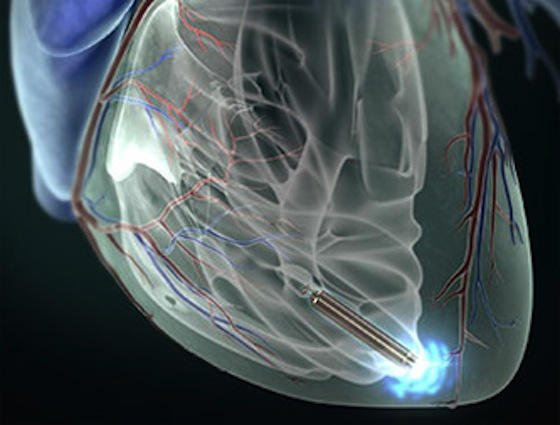

Der Herzschrittmacher Nanostim wird ohne Operation über ein Katheder direkt ins Herz eingeführt. Ohne Verkabelung stimuliert er den Herzmuskel, die Batterie hält 13 Jahre lang.

Foto: St. Jude Medical

Vorsichtig schiebt der Kardiologe den Katheter in die Beinvene. An seiner Spitze ist ein kaum zigarettengroßes Gerät befestigt, der weltweit erste Schrittmacher, der direkt im Herzen platziert wird.

Konzentriert verfolgt der Operateur auf seinem Monitor den Weg des Katheters durch den Körper des Patienten. In der rechten Herzkammer angekommen löst er Nanostim Leadless Cardiac Pacemaker, wie der Schrittmacher heißt, vom Katheter und zieht diesen zurück. Das Gerät registriert die Herztätigkeit und gibt elektrische Impulse ab, wenn der Rhythmus nicht mehr stimmt. Bis zu 13 Jahre lang hält die Batterie. Dann wird das Gerät auf dem gleichen Weg entnommen und durch ein frisches ersetzt. Die minimal-invasive Operation dauert im Durchschnitt nur knapp 30 Minuten.

Der Herzschrittmacher Nanostim wird ohne Operation über ein Katheder direkt ins Herz eingeführt. Ohne Verkabelung stimuliert er den Herzmuskel, die Batterie hält 13 Jahre lang.

Quelle: St. Jude Medical